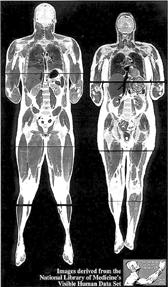

En la imagen se observan los cuerpos de un asesino que fue

ejecutado en Texas y de una ama de casa de Maryland que murió de un

ataque al corazón, los cuales fueron literalmente congelados,

escaneados y fotografiados para ofrecer la visión más cercana jamás

antes obtenida del cuerpo humano. Ambas personas donaron sus cuerpos a

la ciencia Ť Foto: Reuters